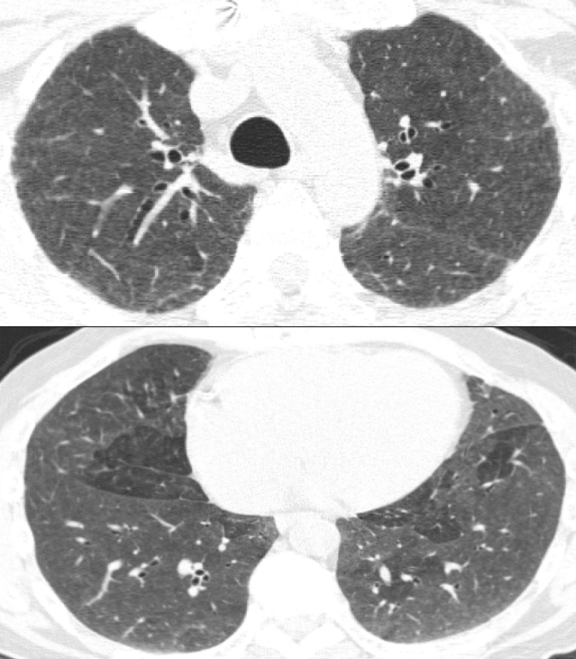

病例:男性,33岁,劳力性呼吸困难4年,加重3月,在治疗之前,我们看到的影像有些磨玻璃影、马赛克征,还有小叶中央型结节,并进行了外科肺活检。患者在从事铸造工作过程中间断接触异氰酸酯。停止工作暴露,并糖皮质激素经过治疗后,病情好转,但停用激素后又出现了肺部弥漫的磨玻璃影,肺功能也有所下降。

图:(从左至右)治疗前、脱离暴露+激素治疗10月、停激素18月